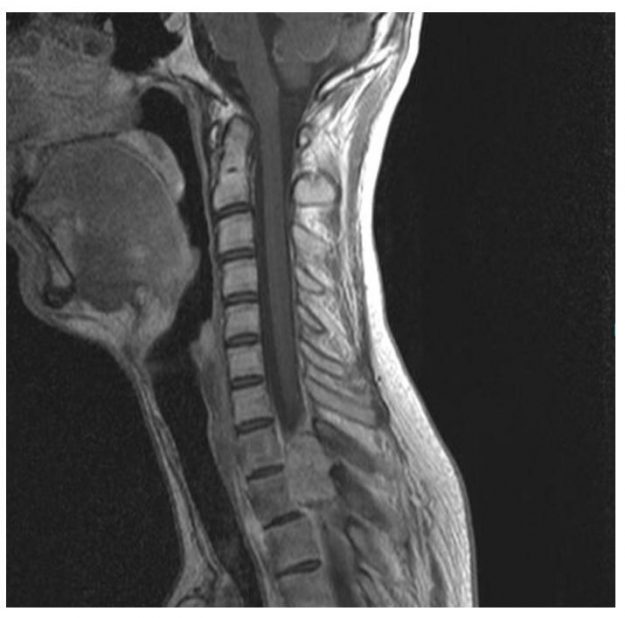

Μετάσταση 10ου Θωρακικού Σπονδύλου (Θ10)

Ασθενής άνδρας 72 ετών με έντονη ραχιαλγία και ιστορικό καρκίνου του πνεύμονα. Ο απεικονιστικός έλεγχος με μαγνητική και αξονική τομογραφία της σπονδυλικής στήλης ανέδειξε μάζα κυρίως στο σώμα του 10ου θωρακικού σπονδύλου (Θ10) με περιβρογχισμό και πίεση επί του νωτιαίου μυελού. (Σημειώστε και τη διήθηση του Θ9 σπονδύλου, χωρίς οστεόλυση). Διενεργήθη αποσυμπίεση του νωτιαίου μυελού…